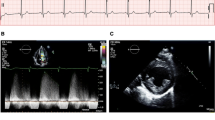

The prevalence of LVH increases with age in patients treated and untreated with enzyme replacement therapy (ERT). Concentric LV remodelling precedes overt left ventricular hypertrophy, but when hypertrophy is established, it can be clinically indistinguishable from other causes of left ventricular hypertrophy including hypertrophic cardiomyopathy (HCM) (Putko et al. 2015; Linhart et al. 2000). Other causes for concentric LV remodelling and hypertrophy include hypertension, aortic valve disease or cardiac amyloidosis. The LVH pattern in AFD can be asymmetric, eccentric, distal or concentric although a concentric pattern of hypertrophy is the most prevalent (Fig. 2a–e) (Wu et al. 2010; Kampmann et al. 2008). 2.2% of patients develop asymmetric septal hypertrophy with a septal to posterior wall dimension ratio > = 1.5 (Wu et al. 2010). Right ventricular hypertrophy (RVH) also develops in as many as 25% of patients with a similar prevalence in men and women (Wu et al. 2010; Palecek et al. 2008).

(Echocardiogram features of Anderson-Fabry disease). a Transthoracic echocardiogram (TTE) parasternal long-axis view (PLAX) demonstrating concentric LVH with an interventricular septum (IVS) and left ventricular posterior wall (LVPW) diameter of 16 mm. b Apical 4 chamber view on TTE demonstrating the presence of concentric LVH. c Moderately dilated left atrium (31 cm2) on apical 4-chamber TTE view. d TTE parasternal short-axis view (PSAX) at mid-ventricular level demonstrating concentric LVH and hypertrophied papillary muscles. e TTE subcostal view demonstrating concentric LVH. f Pulsed wave Doppler across mitral valve inflow demonstrating impaired relaxation (grade 1 diastolic dysfunction) with E:A ratio of 0.87

Diastolic dysfunction and restrictive physiology

Imaging modalities including pulsed wave Doppler and tissue Doppler imaging may be used in the echocardiographic assessment of diastolic function in AFD patients although more sensitive markers include global diastolic strain rate analysis. Diastolic dysfunction is common and results in impaired ventricular filling due to increased ventricular stiffness and impaired relaxation (Fig. 2f). Diastolic dysfunction is probably the commonest cause of exertional dyspnoea and reduced exercise tolerance in patients and may be present before the development of overt LVH (Pieroni et al. 2003). In general, diastolic dysfunction progresses in parallel with ventricular hypertrophy, but rarely, patients can develop severe diastolic dysfunction with a restrictive filling pattern or rising pulmonary pressures that is associated with a poor prognosis. NT-proBNP levels demonstrate a significant positive correlation with LV diastolic dysfunction and are a sensitive marker in detecting early cardiac changes (Torralba-Cabeza et al. 2011).

Diastolic dysfunction contributes to left atrial enlargement which in turn predisposes to atrial arrhythmias including atrial fibrillation (Fig. 2c) (Wu et al. 2010; Weidemann et al. 2003). Left atrial enlargement, increased left atrial stiffness index and reduced atrial compliance also occurs, even in the absence of LVH suggesting an impact on atrial myocardial function and properties early in the disease phase (Boyd et al. 2013). Left atrial volume is usually less dilated than in patients with HCM but speckle tracking demonstrates an atrial cardiomyopathy in Fabry affecting the three phasic functions of the left atrium (Saccheri et al. 2018). This impact on atrial size and function may be due to raised LV filling pressures passively transmitted to the left atrium or due to glycosphingolipid deposition in the left atrial myocardium associated with interstitial fibrosis (Chimenti et al. 2010). Over a third of patients on ERT have evidence of left atrial enlargement (Wu et al. 2010).